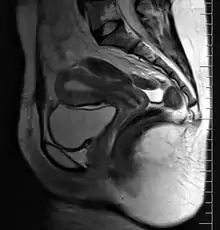

A pictorial illustration of the female reproductive system | |